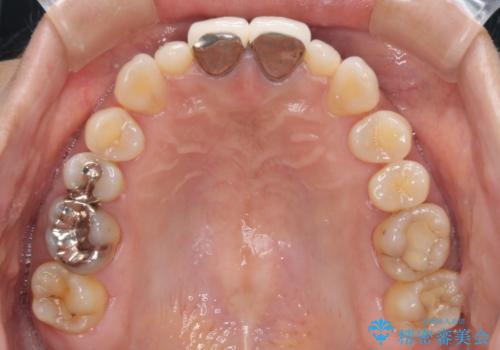

前歯をメタルフリーに 根管治療で不安を取り除いてから

- 他院で奥歯に虫歯があると言われて、ご来院された患者様です。チェックしたところ、奥歯に虫歯は認められませんでした。

前歯に違和感や根尖病巣(根の先に細菌が溜まっている)が認められたため、治療をご提案しました。

セラミック治療と根管治療を行いました。

- 26万円(根管治療は別途。詳細は下記に記載。)費用は治療当時の料金となります

患者様は、もともと奥歯の虫歯を心配してご来院されましたが、前歯に問題が見つかりました。

金属を使用したメタルボンドクラウンが入っていたため、いつかオールセラミックにしたいときに根管治療も行ったほうが良いとご提案し、今回行いました。

就寝時マウスピース(約5000円別途)の使用をおすすめしました。